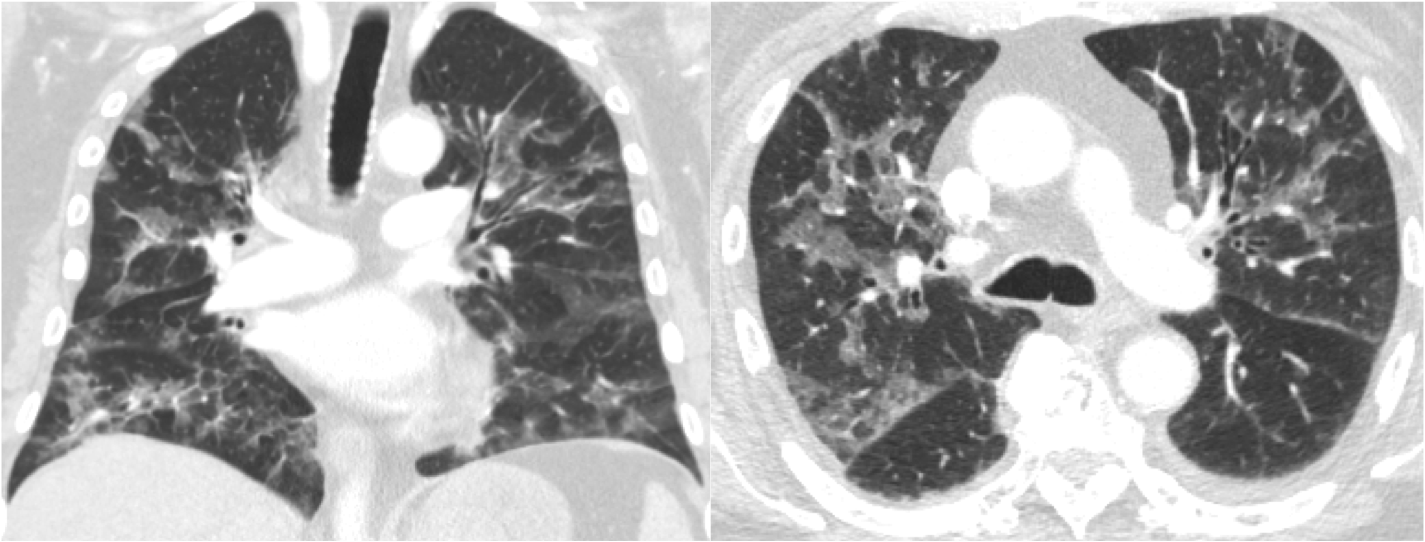

The study compared PET/CT tracers over 18F-fluciclovine when it comes to the localization of biochemical recurrence of prostate cancer following radical prostatectomy.